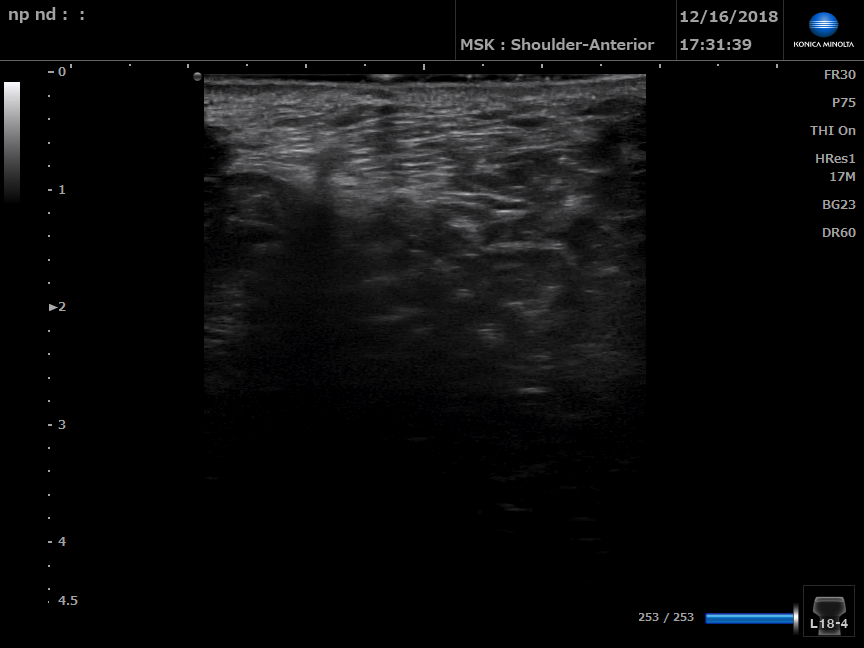

B Mode ultrasound of left perineal body

B Mode ultrasound of right perineal body